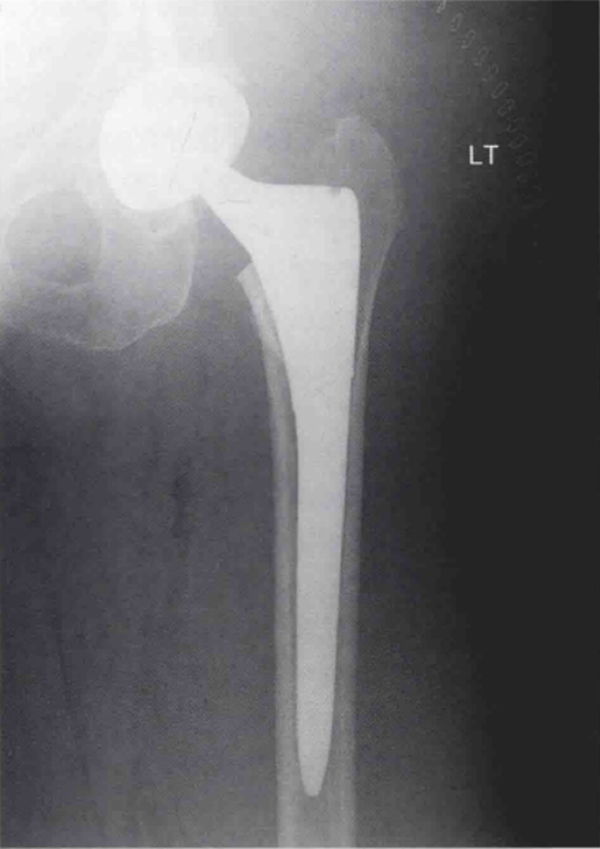

术后常规X线检查显示股骨近端可疑无移位骨折(图1和图2)。CT扫描证实了骨折的存在,且已对假体柄的稳定性造成了影响(图3)。

图1 初次全髋关节置换术后左髋正位X线片,显示股骨近端一处可疑无移位骨折